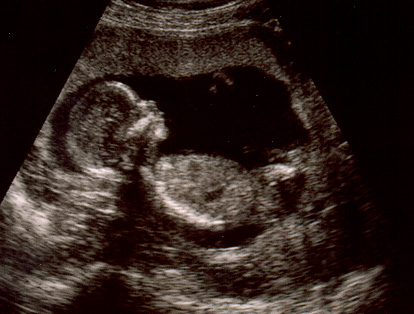

13.

haftada yaptırdığımız üçlü testin sonucu 1/1700 çıkmıştı, bu çok iyi bir

sonuçmuş. Yani, 1.700’de 1 oranda sorun çıkma ihtimali var demekmiş. Bu

hafta yaptıracağımız entegre testte de aynı iyi sonuç çıkarsa, amniyosentez

istemeyeceğini söyledi doktorumuz. Bu

tarama testlerinde doktorumuz karnımda bayağı zaman geçiriyor ultrasonla, bu da

bebeği görmek ve izlemek için çok iyi bir fırsat.

Randevuya

kocam, ablam, yeğenim ve onun en iyi arkadaşı ile gittik! Hepimizin gözü

monitörde, ben ağlıyorum, kızlar filme alıyor, doktorumuz pür dikkat, kocamın

eli elimde…